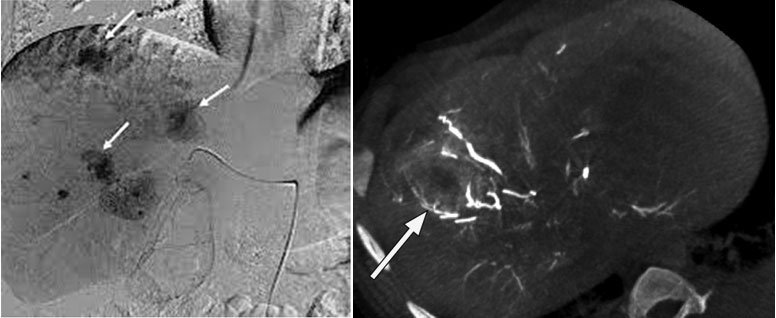

It is a localized method of administrating chemotherapy directly to the liver tumor via a catheter. One key advantage is the chemotherapy is targeted locally so reducing the systemic side effects of intravenous chemotherapy.

A small puncture is made in blood vessel of thigh region with needle through which wire passed and sheath placed.

Angiography done with catheter under X-ray guidance to look for abnormal region of liver, once we identify the feeding vessels, catheter is placed and blocking agent placed in it.

During procedure (showing HCC)

Follow up CT after procedure